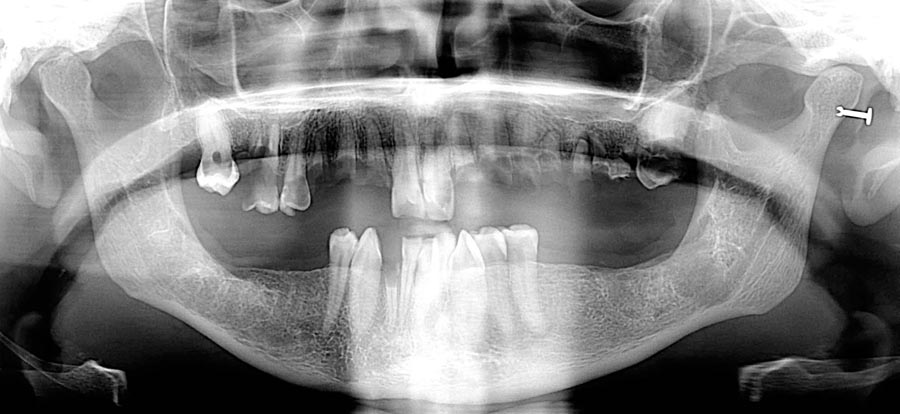

Her panoramic radiograph shows multiple missing and broken teeth along with tooth decay and areas of infection spreading into the bone.